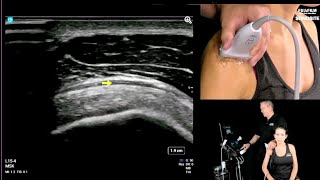

Carpal Tunnel Evaluation

January 29, 2021

Education

With Daniel Shelton, RT(R)

Watch now